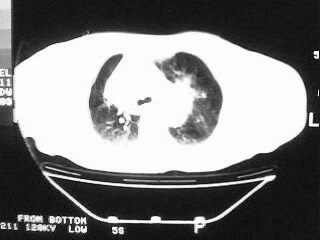

女,79,咳 嗽月余,无其它不适

1)两肺炎症。2)食管裂孔疝可能;建议行上消化道钡餐检查。

后纵隔内左心房至肝左叶后方椎体中线偏左巨大软组织包块,其壁均匀比较薄,其内可见宽气液平。

考虑食管裂孔疝。建议钡餐检查